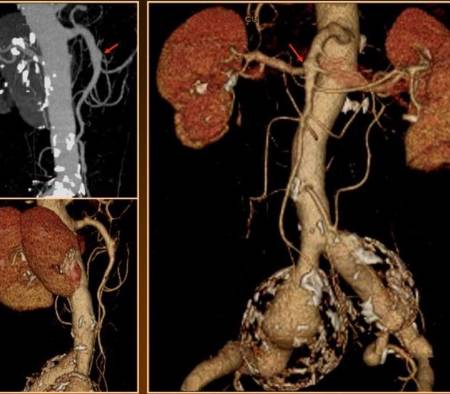

Aneurismas viscerales: importancia, detección y tratamientos

Hoy en día, las pruebas de imagen no invasivas permiten detectarlos antes de que se compliquen irremediablemente. En palabras del especialista, "la tomografía computarizada (TC) es la mejor prueba diagnóstica para estas patologías, frente a la ecografía que es menos sensible. Por otro lado, arteriografía permite valorar la colateralidad, cosa que es particularmente útil en aquellos casos en los que sea necesario ligar u ocluir la arteria".